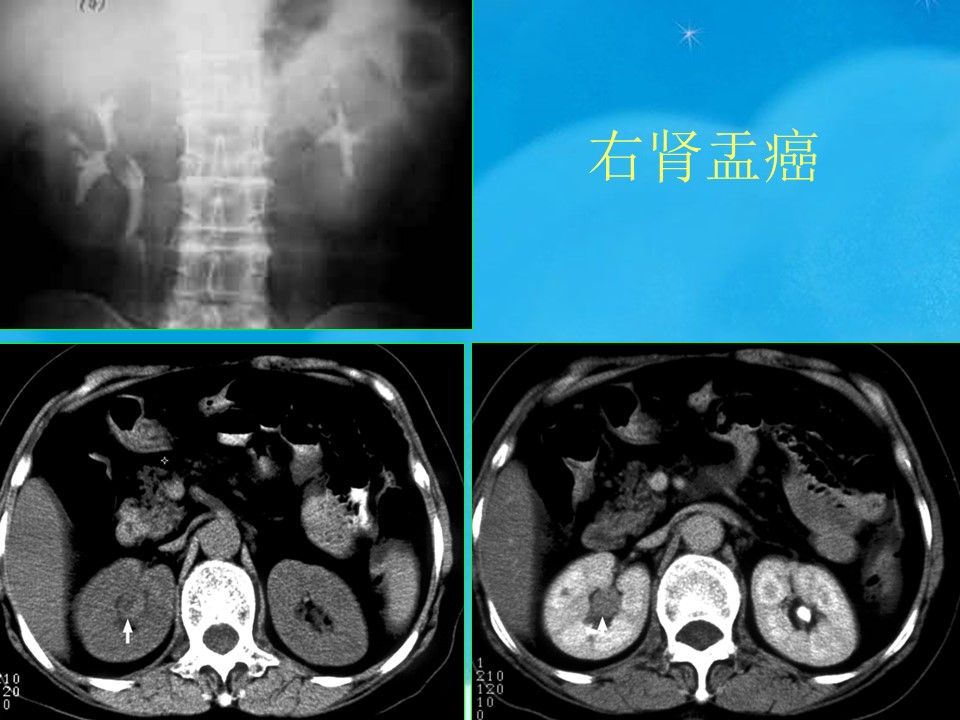

“腹部、盆腔影像诊断学PPT” 的相关文章